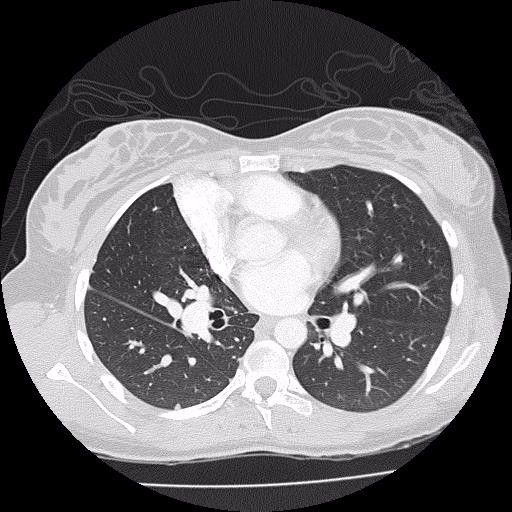

Axial view of HRCT chest. Hrct Chest X Ray Near Me in most cases, physicians who manage patients with dild will request a. hrct provides superior evaluation of lung abnormalities. Subpleural honeycombing (red arrow), traction. ideally, an expiratory hrct scan should be performed in all obstructive airway diseases. Hrct Chest X Ray Near Me.